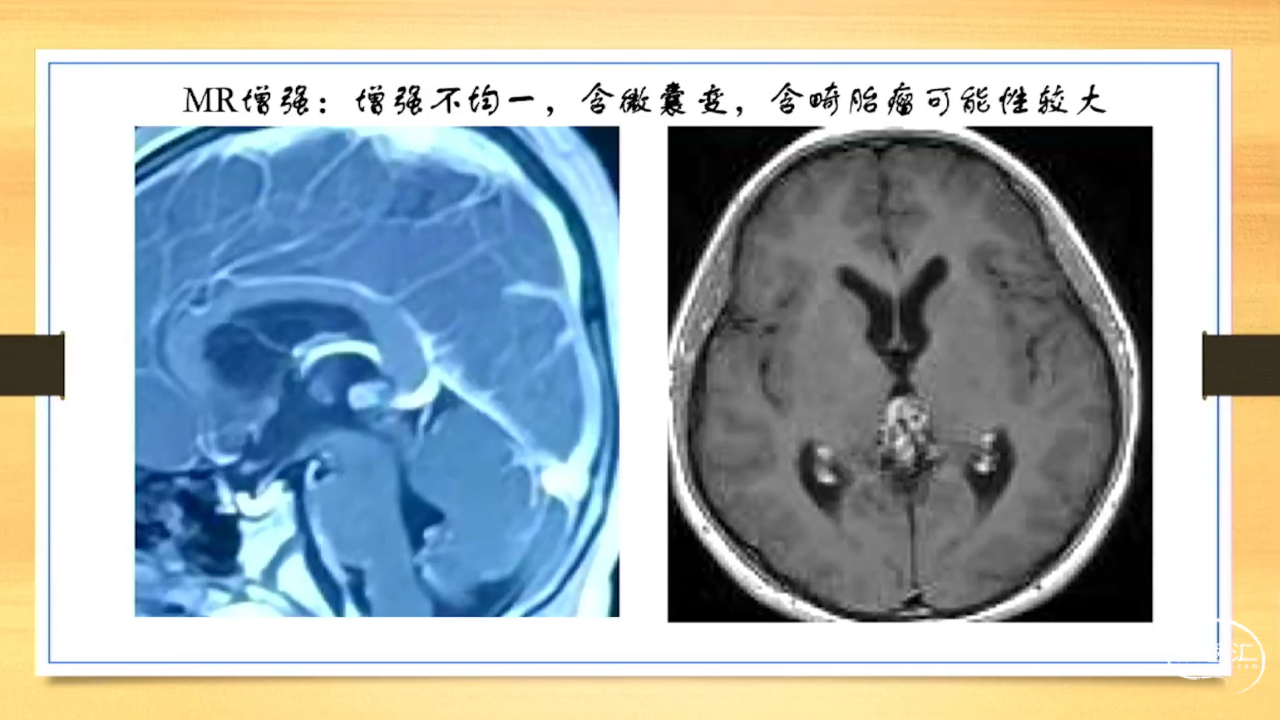

张荣教授:儿童颅内生殖细胞瘤的手术治疗

颅内生殖细胞肿瘤的治疗是手术、放疗、化疗、内分泌及其他多学科的整合治疗。及时、精准、合理的手术治疗是iGCT患者提高生存率、降低并发症、改善神经内分泌功能的关键。